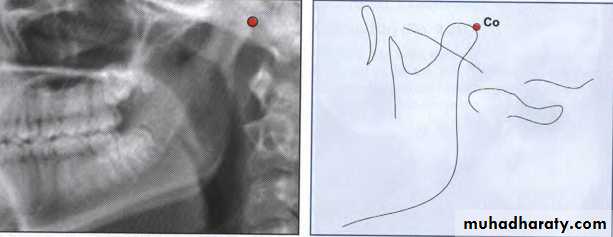

Condylion (Co)

Condylion is the most posterosuperior point on thecondyle of the mandible.